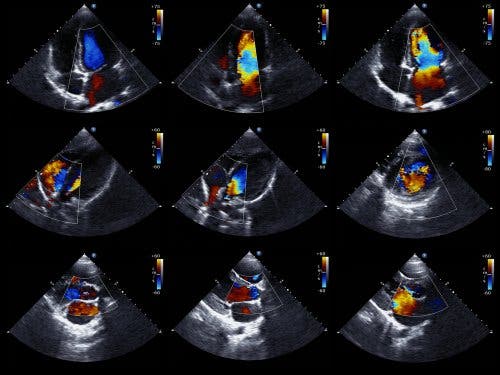

Ekokardiyogram, perikardiyal efüzyon varlığını saptamak için tercih edilen testtir. Aynı zamanda ekokardiyografi ya da kalp ultrasonu olarak da adlandırılır ve doktorların kalbin yapısını görmesine ve kan pompalama yeteneğini incelemesine izin veren bir testtir.

Ayrıca Doppler ekokardiyogramı da doktorların kalpten kan akışının tam hızını belirlemesine olanak tanır. Teknik bir açıdan bakıldığımda, iki boyutlu ve M-mod ekokardiyogram, perikardiyal efüzyon varlığını teşhis etmek, ölçmek ve takip etmek için ideal bir tekniktir.

Epikardiyum ve lateral perikardiyum arasında eko yokluğunun bulunması, doktorların perikardiyal efüzyon teşhisi koymasına olanak tanır. Daha sonra kardiyolog, perikardın iki katmanı arasındaki boşluk miktarına göre efüzyonun boyutunu belirler.

Temelde iki tür ekokardiyogram olduğunu da söylemeliyiz. Göğse, kalbin üzerine denk gelecek şekilde bir cihazın yerleştirildiği ve ses çıkardığı transtorasik ekokardiyogram vardır. Ve cihazın sindirim sistemine, yemek borusuna kadar yerleştirildiği transözofageal ekokardiyogram vardır. İkincisi, daha ayrıntılı veriler sağlar.